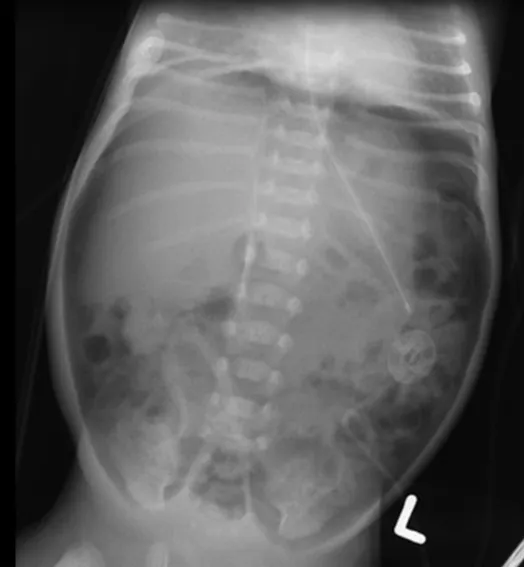

22-2 ACM : 신생아 중환자실에서 입원 치료 중인 생후 21일 된 신생아가 담즙 섞인 구토를 한다. 임신나이 29주, 출생체중 1,280 g으로 출생하였다. 출생 직후 호흡곤란증후군으로 폐표면활성물질 치료를 받았고 기계 환기 중이며, 생후 2일째 부터 입위관을 통하여 분유를 주입받고 있다. 신체진찰에서 복부 팽만이 관찰된다. 복부 X선사진이다. 치료는?

: 응급 개복수술 vs 금식 및 경과 관찰

AXR상 간 위쪽으로 공기음영이 관찰되는 pneumoperitoneum이 확인된다. 장천공이 있다는 뜻이므로 응급개복수술을 시행